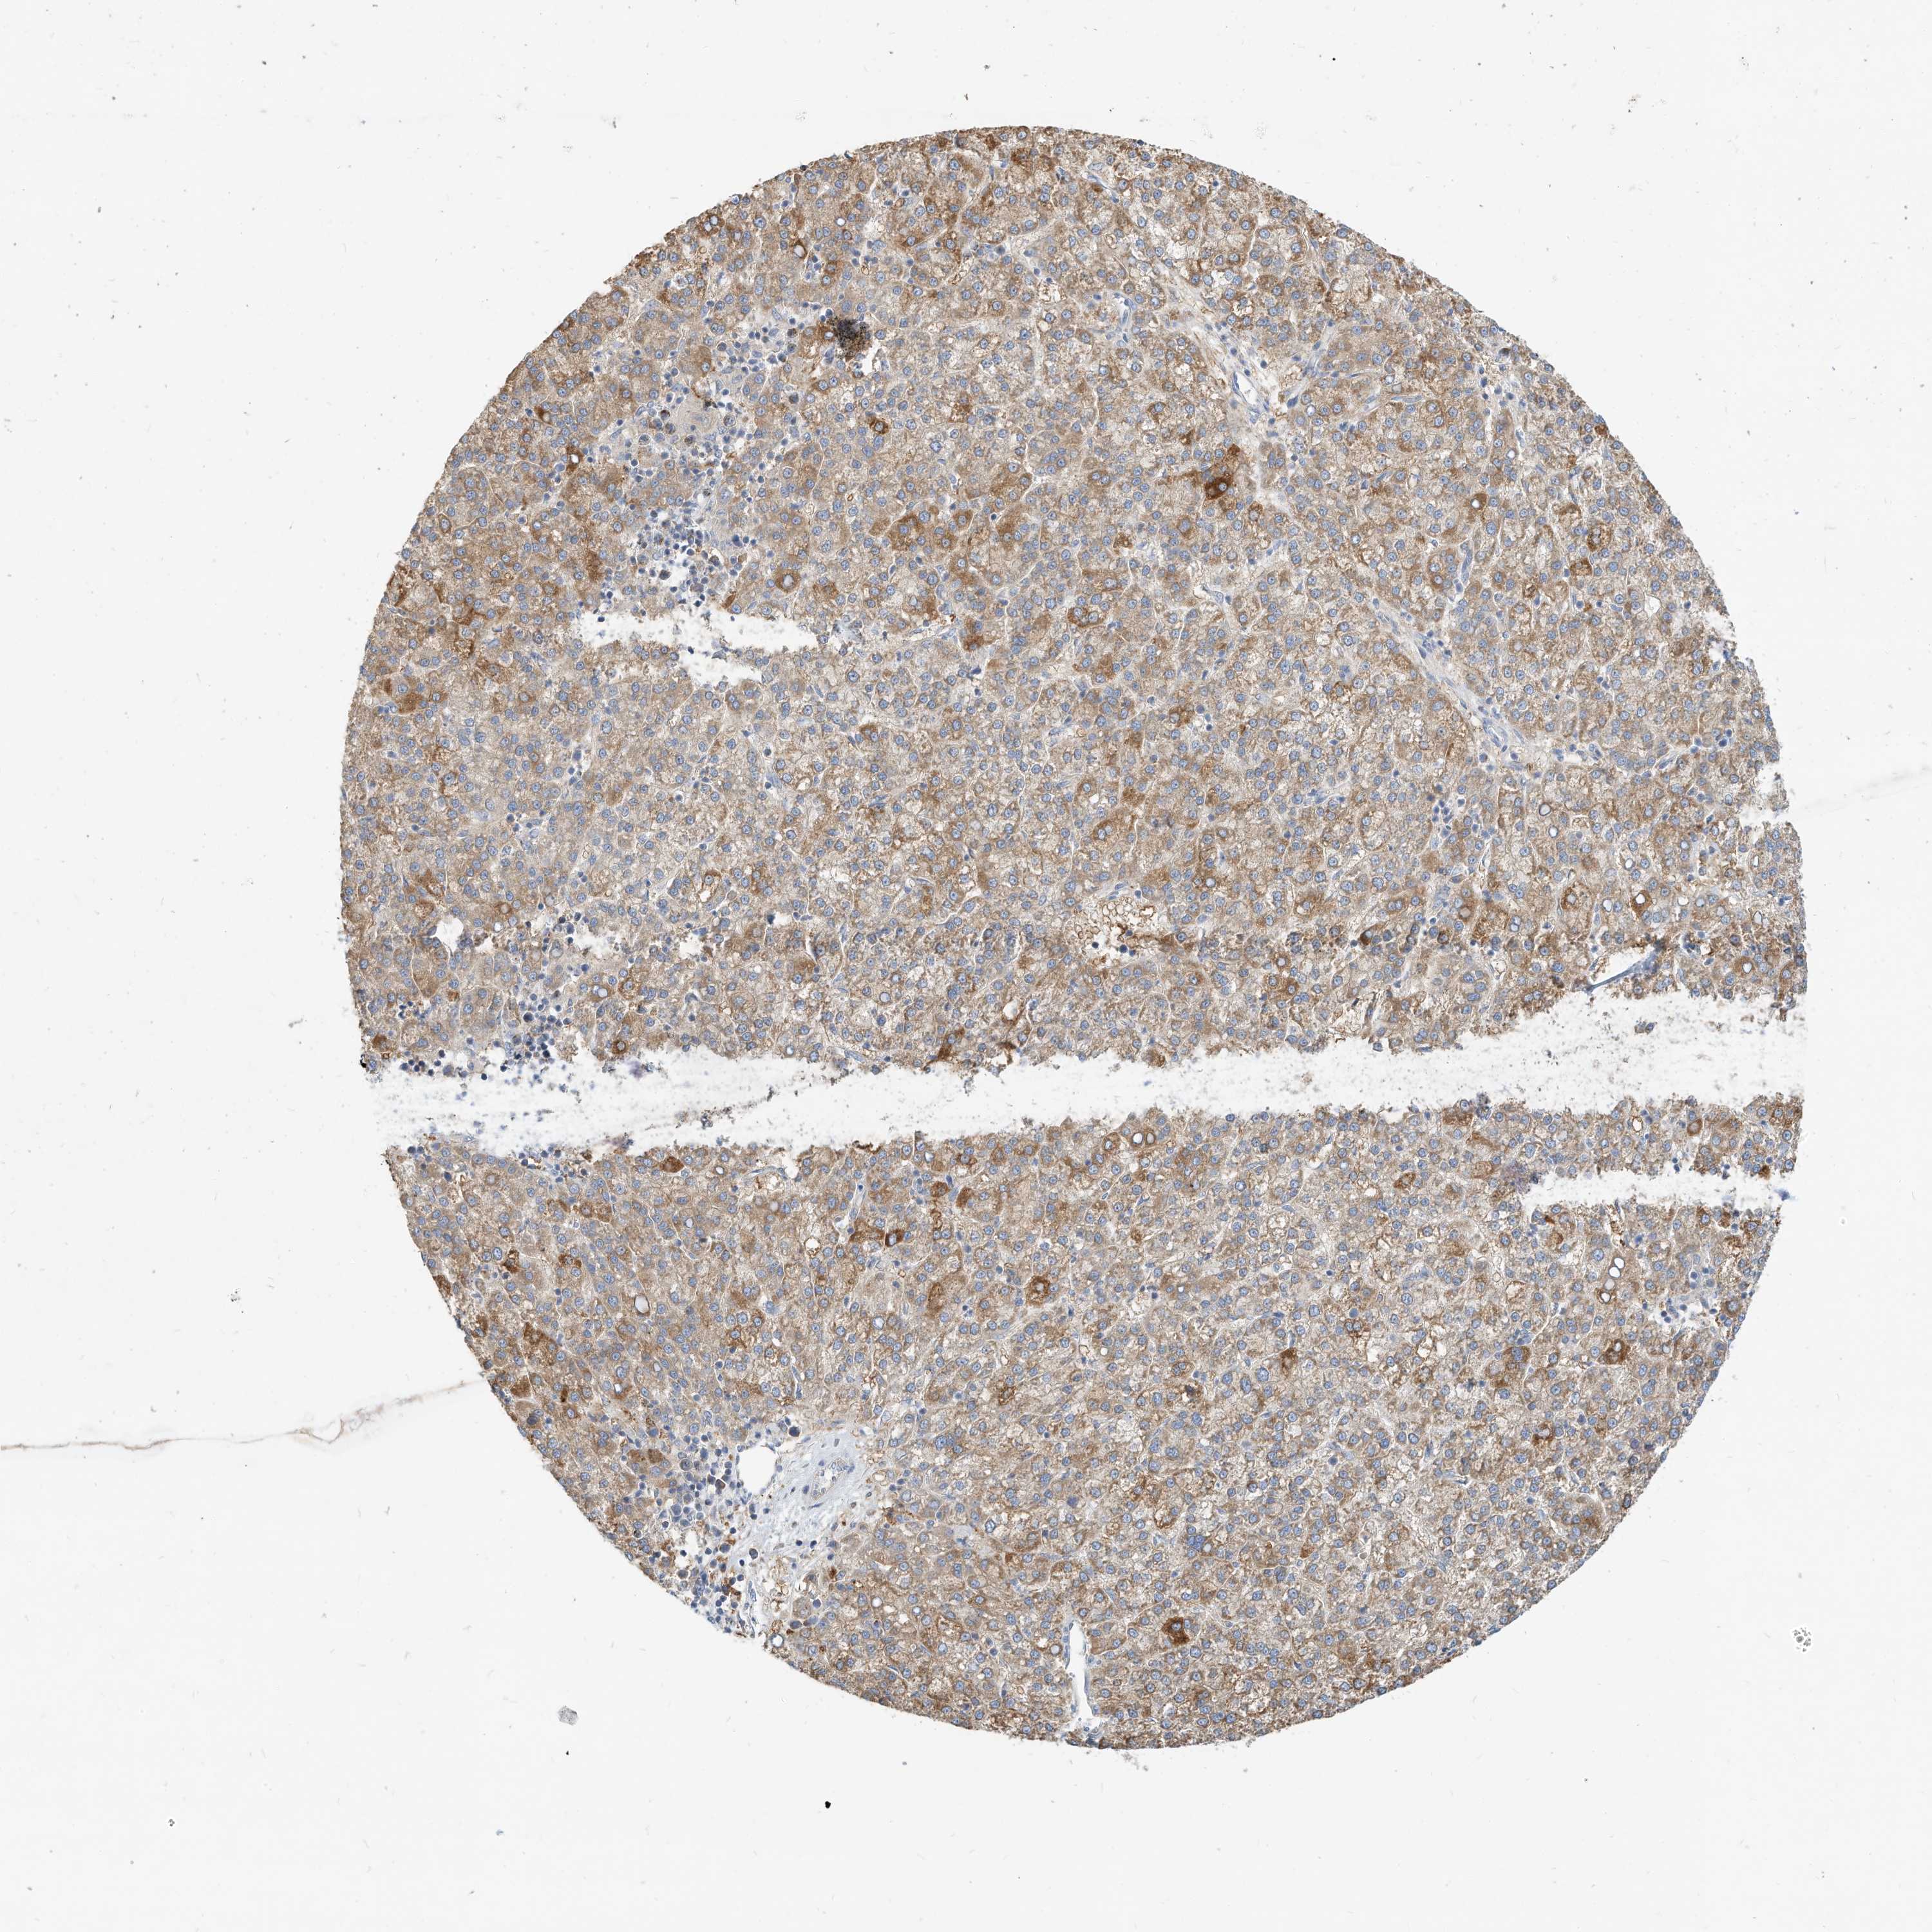

LIVER CANCER - Protein expressioni

A mouse-over function shows sample information and annotation data. Click on an image to view it in a full screen mode. Samples can be filtered based on level of antibody staining by selecting one or several of the following categories: high, medium, low and not detected. The assay and annotation is described here.

Note that samples used for immunohistochemistry by the Human Protein Atlas do not correspond to samples in the TCGA dataset.

Antibody stainingi

Antibody staining in the annotated cell types in the current human tissue is reported as not detected, low, medium, or high, based on conventional immunohistochemistry profiling in selected tissues. This score is based on the combination of the staining intensity and fraction of stained cells.

Each image is clickable and will lead to virtual microscopy that enables deeper exploration of all samples and also displays staining intensity scores, fraction scores and subcellular localization as well as patient and tissue information for each sample.

Antibody HPA030345

Staining

High

Medium

Low

Not detected

Intensity

Strong

Moderate

Weak

Negative

Quantity

>75%

75%-25%

<25%

None

Location

Nuclear

Cytoplasmic/membranous

Cytoplasmic/membranous,nuclear

Carcinoma, Hepatocellular, NOS